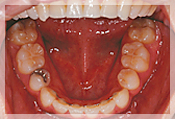

症例4

重度の叢生と上顎前歯の前突症例